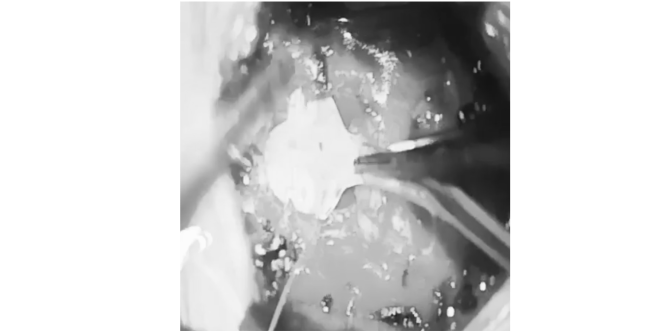

Lesions

Trigeminal neuralgia

Percutaneous Trigeminal Rhizotomy